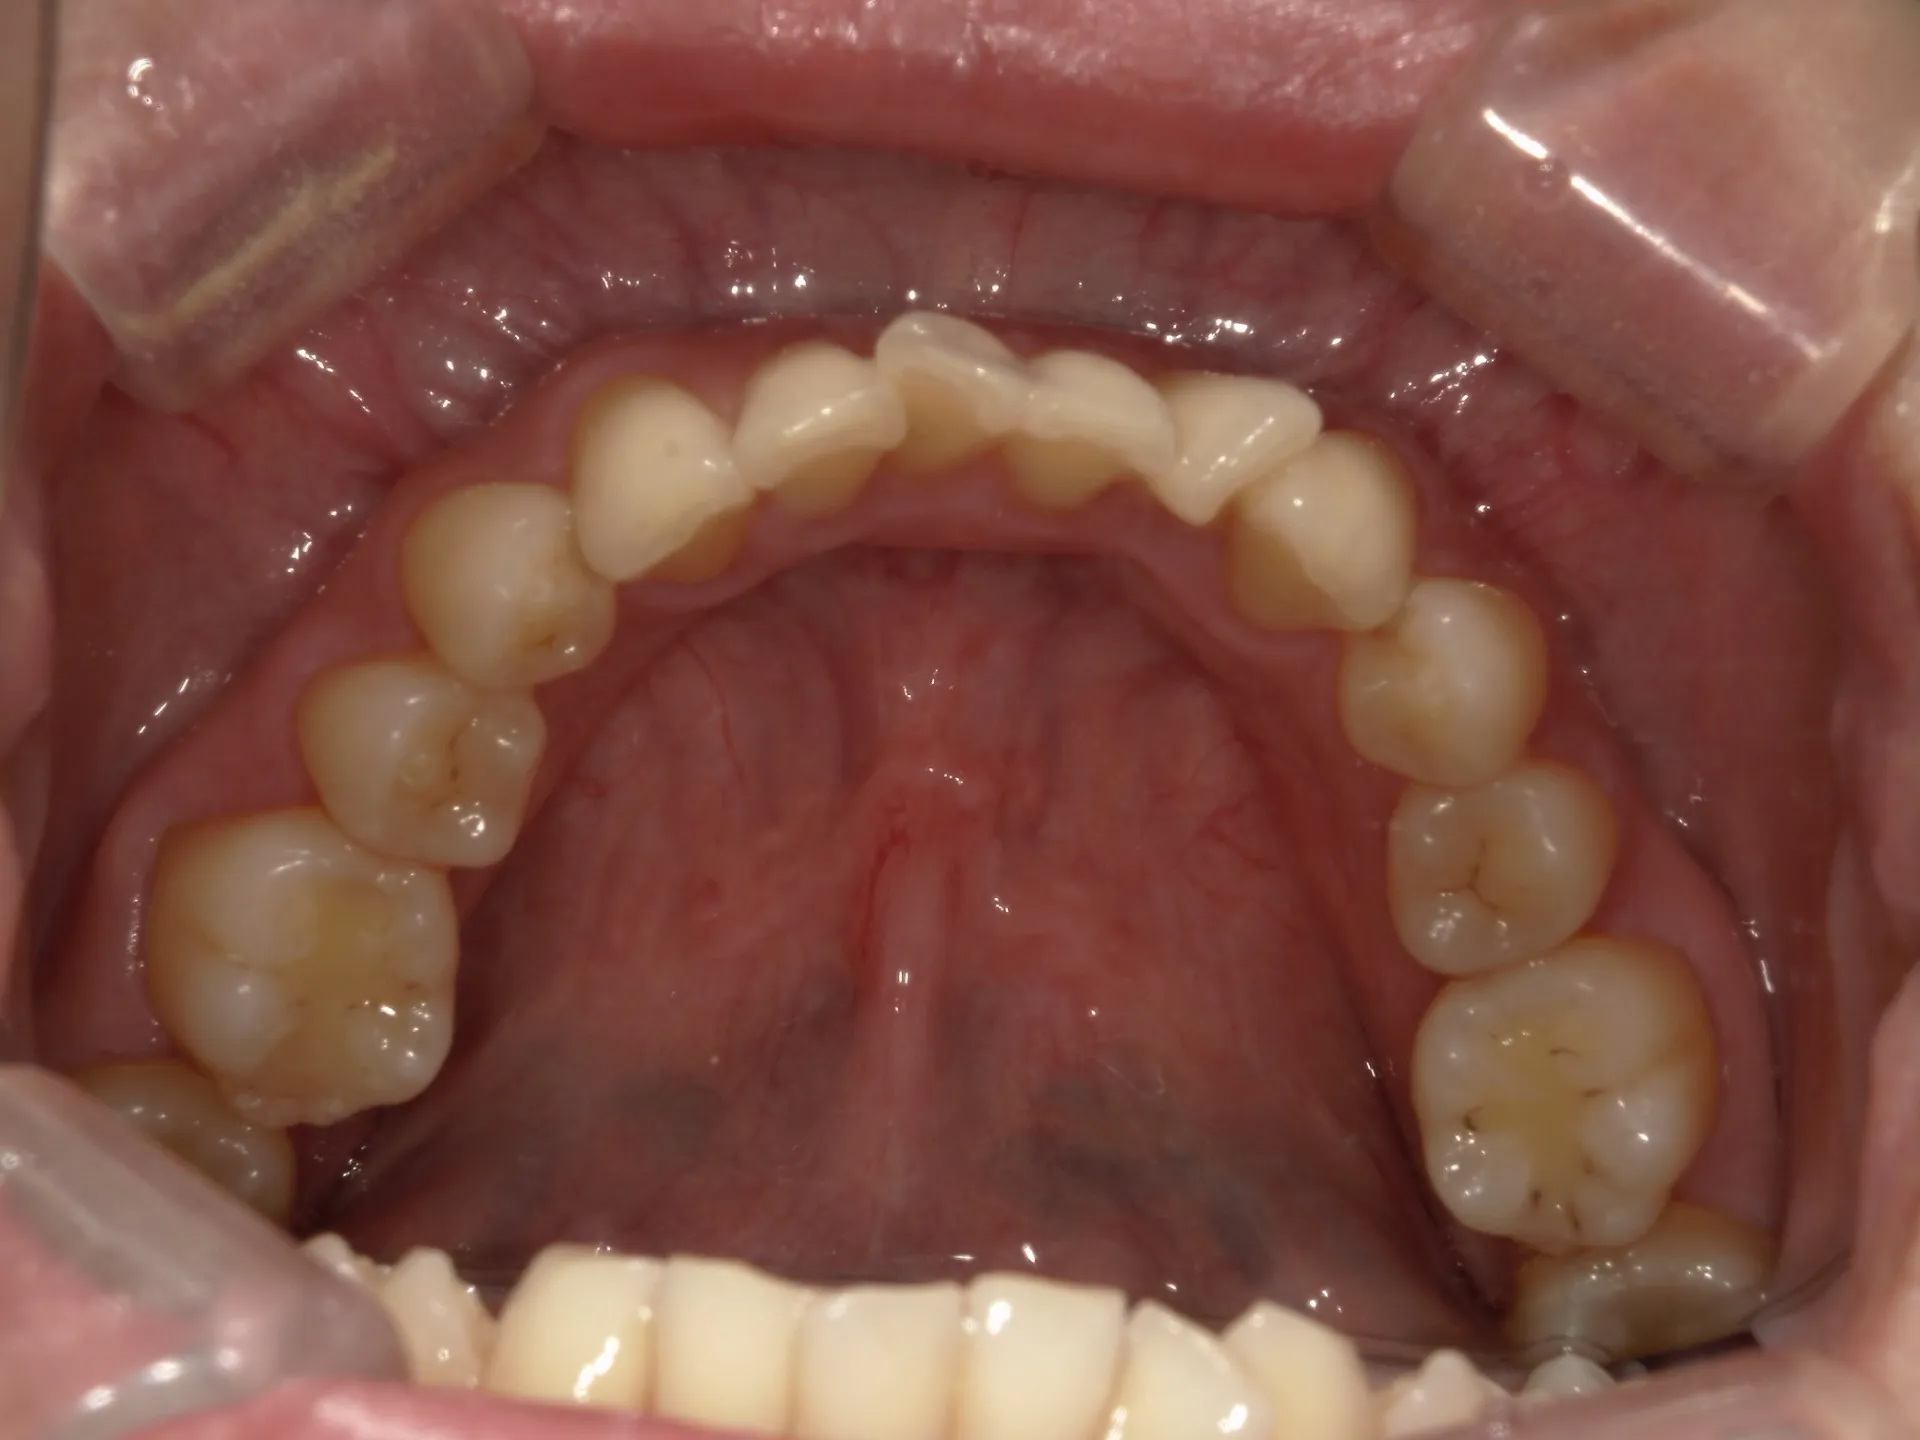

今回はねじれてしまった前歯の矯正治療をインビザラインというマウスピース矯正で治療した症例をご紹介いたします。